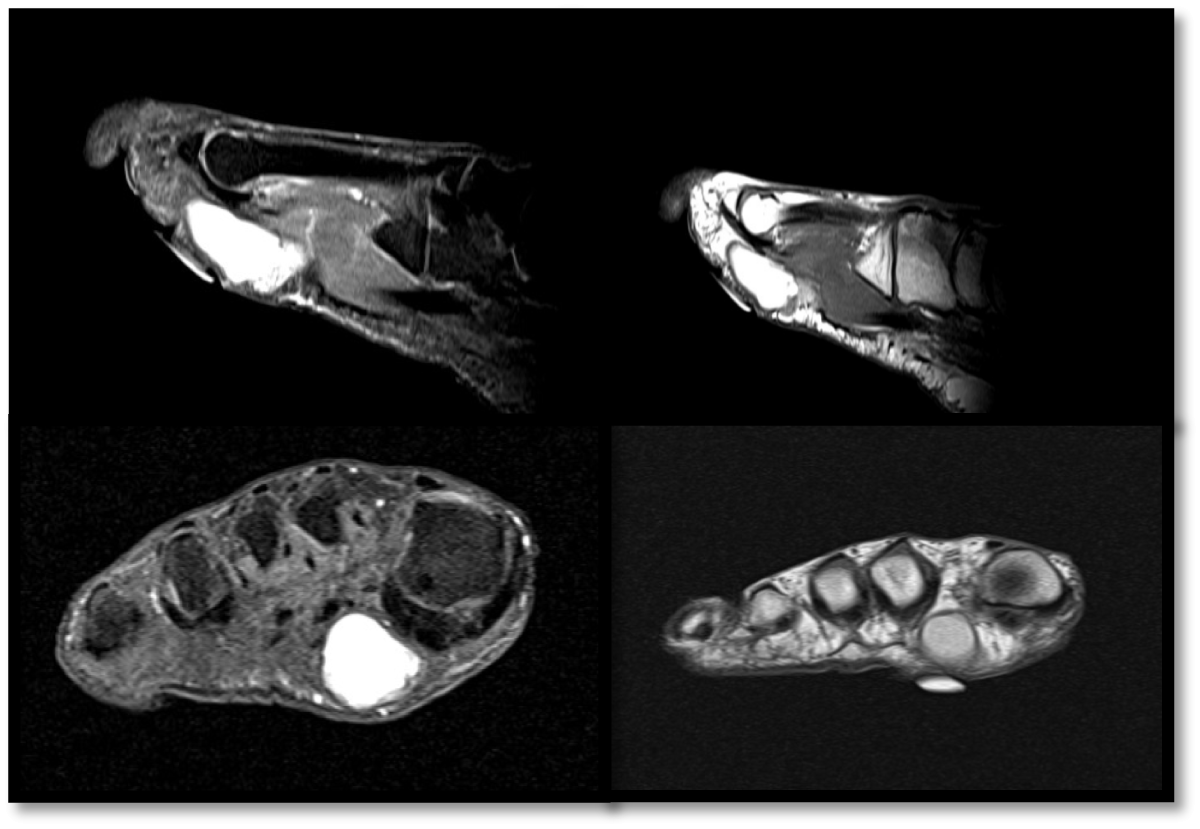

A three-view radiographic examination of the right foot was essentially unremarkable (Figure 1). It showed no evidence of intralesional mineralization, osseous erosion, or remodeling of the metatarsal bones. Afterwards, a magnetic resonance imaging (MRI) of the right foot was conducted revealing a subcutaneous lesion between the distal 1 st and 2 nd metatarsal (Figure 2).

Figure 2: The magnetic resonance images exhibited a demarcated subcutaneous lesion measuring 3.5 × 2.6 × 1.6 cm located in the plantar forefoot at the distal first and second metatarsals, along the plantar aponeurosis. The lesion exhibited a heterogeneous hyperintensity on post-contrast sequences and somewhat hyperintensity on T1. The superficial aspect of the lesion seen 0.3 cm deep the skin surface and is seen abutting the superficial fascia of the lateral head flexor hallucis brevis and flexor digitorum brevis muscles. A cyst-like structure of greater size was observed, likely containing proteinaceous or hemorrhagic material. View Figure 2

MRI is useful in diagnosis due to higher contrast resolution for soft tissue lesions. On MRI, these tumors present as superficial lesions comprising both solid and cystic masses, distinguished by fluid levels in the cystic components and enhancement of the solid components. The cystic components show a range of MRI signal intensities, which is thought to result from differing quantities of cholesterol, hemorrhage, and sweat gland secretions present in the fluid [15]. Although histological examination is mostly used for the confirmation of malignancy. In our case, histologically the lesion had mixed cystic, solid, and mucinous/clear cell areas and lacked significant cytologic atypia, mitotic activity, and necrosis, ruling out malignancy.